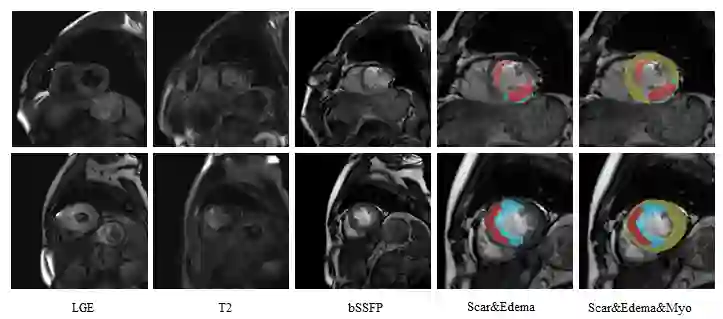

Multi-sequence cardiac magnetic resonance (CMR) provides essential pathology information (scar and edema) to diagnose myocardial infarction. However, automatic pathology segmentation can be challenging due to the difficulty of effectively exploring the underlying information from the multi-sequence CMR data. This paper aims to tackle the scar and edema segmentation from multi-sequence CMR with a novel auto-weighted supervision framework, where the interactions among different supervised layers are explored under a task-specific objective using reinforcement learning. Furthermore, we design a coarse-to-fine framework to boost the small myocardial pathology region segmentation with shape prior knowledge. The coarse segmentation model identifies the left ventricle myocardial structure as a shape prior, while the fine segmentation model integrates a pixel-wise attention strategy with an auto-weighted supervision model to learn and extract salient pathological structures from the multi-sequence CMR data. Extensive experimental results on a publicly available dataset from Myocardial pathology segmentation combining multi-sequence CMR (MyoPS 2020) demonstrate our method can achieve promising performance compared with other state-of-the-art methods. Our method is promising in advancing the myocardial pathology assessment on multi-sequence CMR data. To motivate the community, we have made our code publicly available via https://github.com/soleilssss/AWSnet/tree/master.